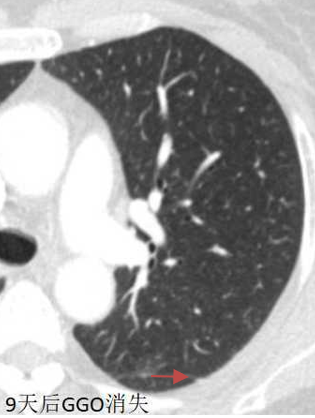

这个患者,单纯门诊定期随访,一年后结节不见了。